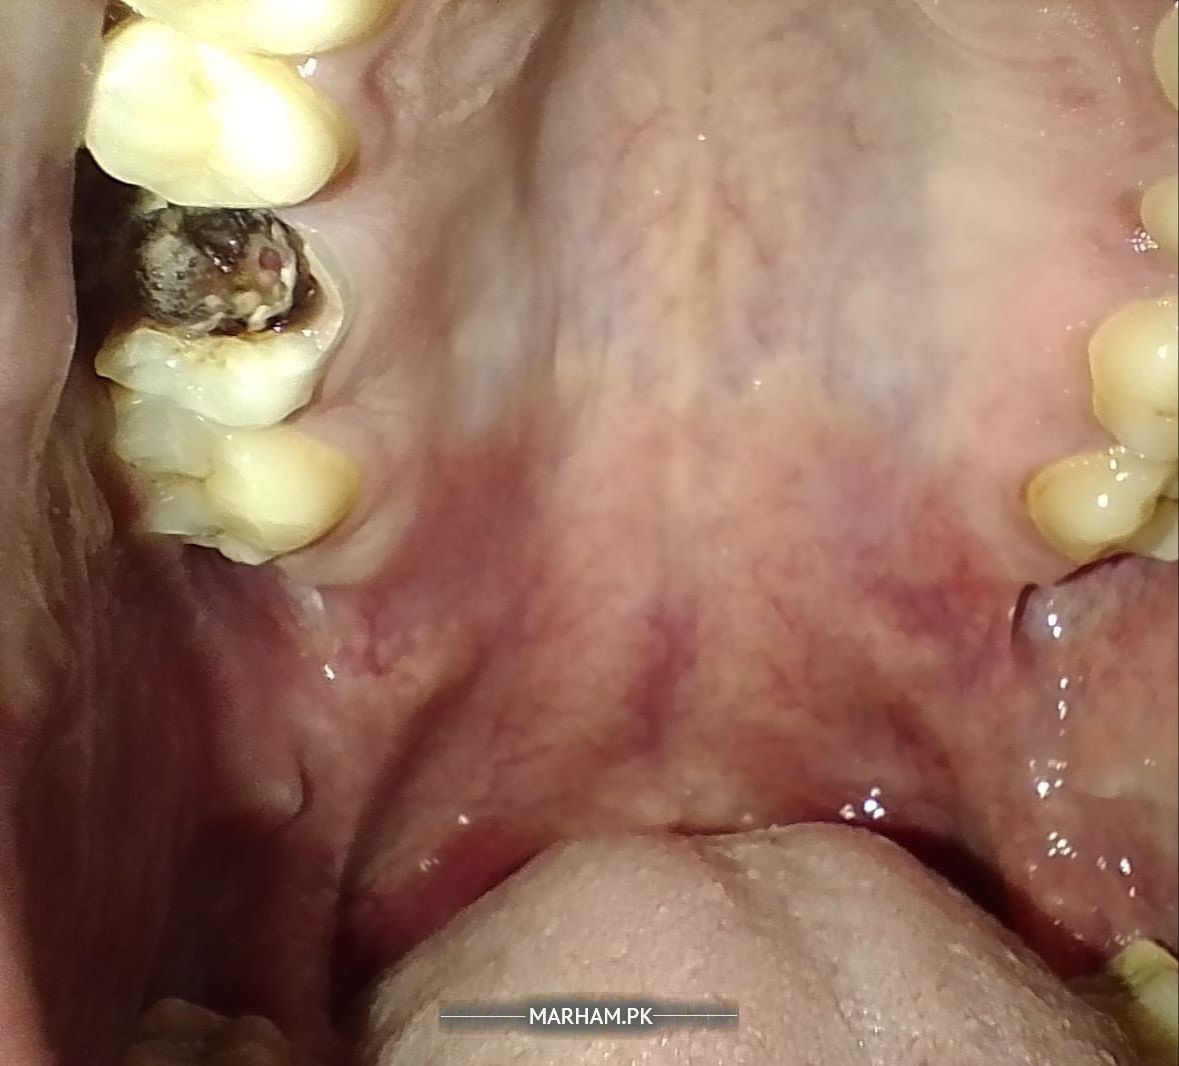

What should be done here? Molar tooth is broken and black inside.

Here is the better pic. This is how it looks. It happened 2 years back for the first time. Since then its breaking away from time to time without any pain.

Assalmualikum. This is a cavity. Looks like it needs root canal treatment. But can be confirmed after xray

Cavity deep hai,samne dekh kar ya xray pr confirm kiya ja sakta hai k root canal treatment possible hai ya extraction hogi ,q ek side dikh nhn rha k kitna deeply carious hai

Please visit the clinic for proper evaluation. Need to check it clinically. Either root canal or extraction as the cavity seems deep.

More than 50% tooth is broken..long term poor prognosis.. sadly u need extraction

u can get a radiograph done to see the extent of caries but looking at the condition it is most like beyong repair and needs extraction to prevent pain in future

Please get a periapical x-ray done for further evaluation. If the lesion is near your roots and tooth structure can be saved, you can opt for a root canal and crown. However, if there is less tooth structure and root canal can't be supported, then extraction.